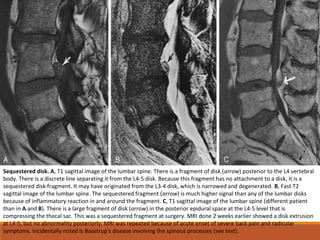

Sequestered disk. A, T1 sagittal image of the lumbar spine. There is a fragment of disk (arrow) posterior to the L4 vertebral

body. There is a discrete line separating it from the L4-5 disk. Because this fragment has no attachment to a disk, it is a

sequestered disk fragment. It may have originated from the L3-4 disk, which is narrowed and degenerated. B, Fast T2

sagittal image of the lumbar spine. The sequestered fragment (arrow) is much higher signal than any of the lumbar disks

because of inflammatory reaction in and around the fragment. C, T1 sagittal image of the lumbar spine (different patient

than in A and B). There is a large fragment of disk (arrow) in the posterior epidural space at the L4-5 level that is

compressing the thecal sac. This was a sequestered fragment at surgery. MRI done 2 weeks earlier showed a disk extrusion

at L4-5, but no abnormality posteriorly. MRI was repeated because of acute onset of severe back pain and radicular

symptoms. Incidentally noted is Baastrup's disease involving the spinous processes (see text).